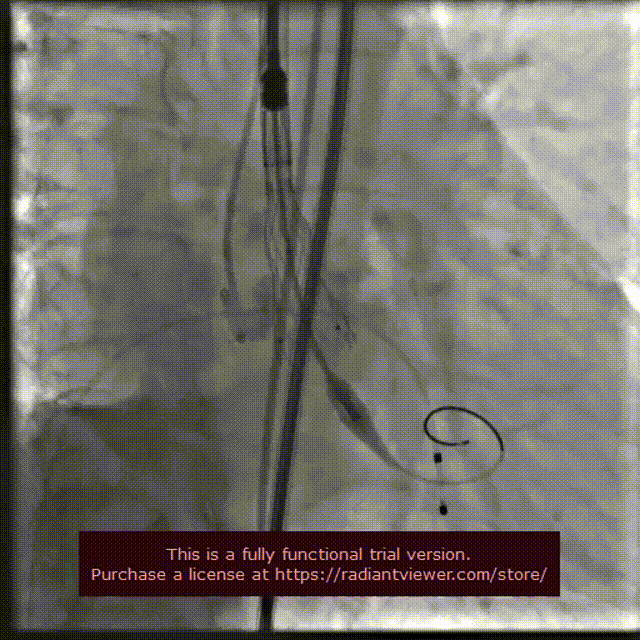

输送系统定位

VenusA-Plus®释放过程

18 mm球囊后扩

瓣膜完整形态

术者团队观察到瓣膜形态未能完全伸展,为取得更好治疗效果,后续予以后扩处理。采用18 mm球囊进行后扩后扩,行主动脉造影提示瓣膜置入位置良好、形态完整。